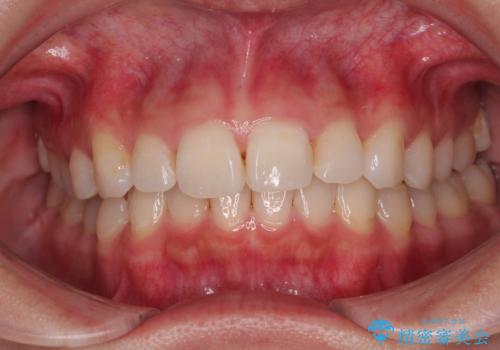

- 前歯のデコボコと突出感を気にして来院された患者様です。

極力目立たない装置を希望とのことで、インビザラインを用いて非抜歯で矯正治療を行うこととしました。

事前に親知らず2本を抜歯し、多少歯列を後方に移動できるように準備をした上で、なるべく歯と歯の間を削ることなくデコボコを解消できるように計画しました。

前歯の捻れを改善するとともに、口元が少しでも引っ込むように治療計画を立て、仕上げることができました。